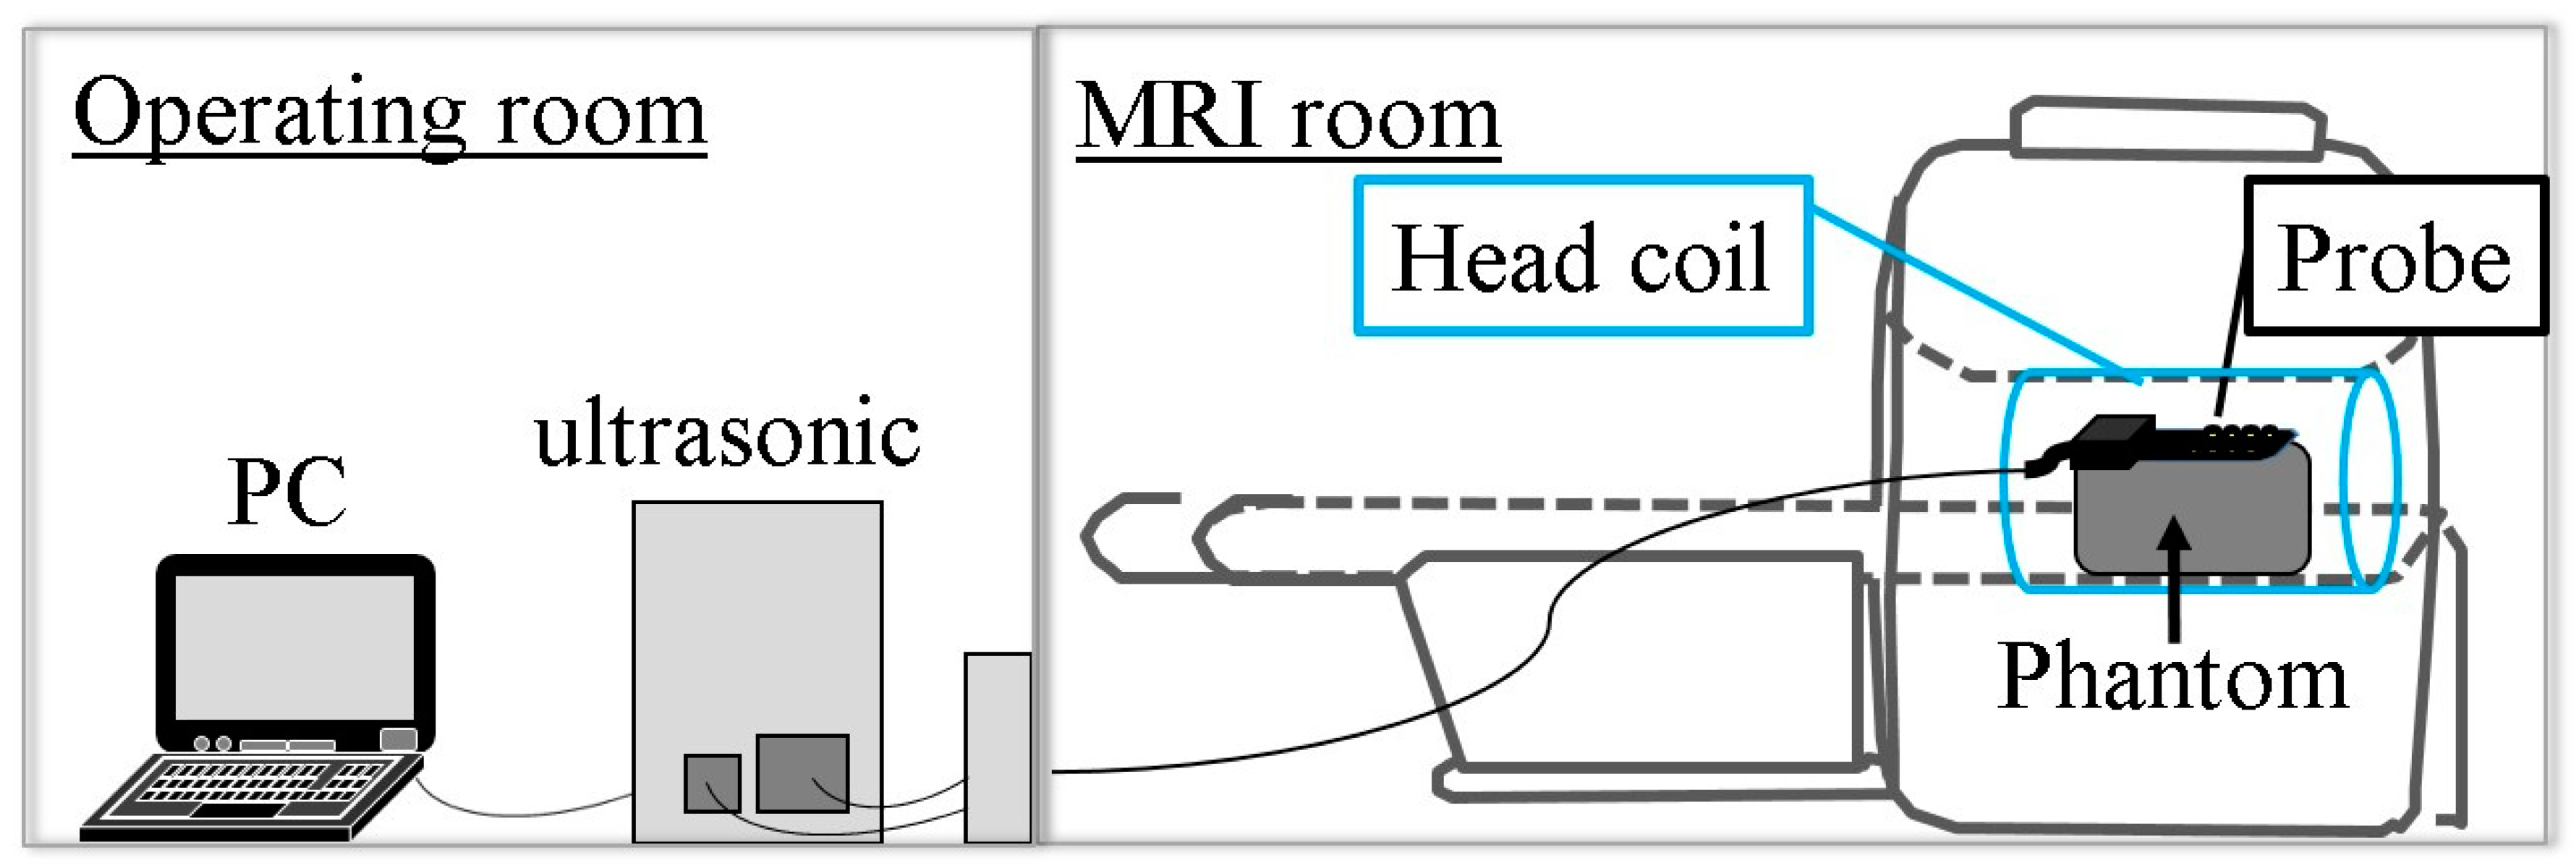

2.2. Simultaneous Multimodality Imaging System Using Ultrasound and Magnetic Resonance